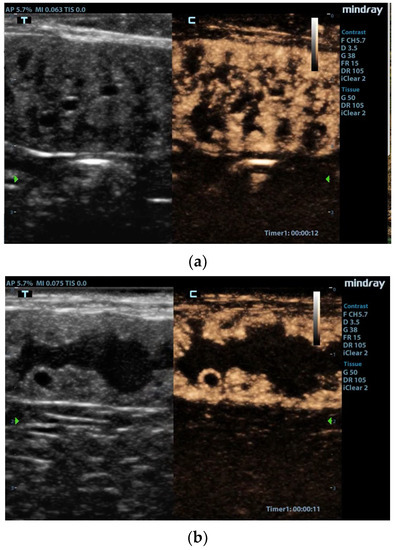

- Quartuccio, M.; Liotta, L.; Cristarella, S.; Lanteri, G.; Ieni, A.; D’Arrigo, T.; De Majo, M. Contrast-Enhanced Ultrasound in Cystic Endometrial Hyperplasia–Pyometra Complex in the Bitch: A Preliminary Study. Animals 2020, 10, 1368. [Google Scholar] [CrossRef] [PubMed]